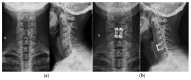

Osteoarthritis is a degenerative condition affecting the whole joint with the underlying bone, representing a major source of pain, disability, and socioeconomic cost worldwide. Age is considered the strongest risk factor, albeit abnormal biomechanics, morphology, congenital abnormality, deformity, malalignment, limb-length discrepancy, lifestyle, and injury may further increase the risk of the development and progression of osteoarthritis as well. Pain and loss of function are the main clinical features that lead to treatment. Although early manifestations of osteoarthritis are amenable to lifestyle modification, adequate pain management, and physical therapy, disease advancement frequently requires surgical treatment. The symptomatic progression of osteoarthritis with radiographical confirmation can be addressed either with arthroscopic interventions, (joint) preservation techniques, or bone fusion procedures, whereas (joint) replacement is preferentially reserved for severe and end-stage disease. The surgical treatment aims at alleviating pain and disability while restoring native biomechanics. Miscellaneous surgical techniques for addressing osteoarthritis exist. Advanced computer-integrated surgical concepts allow for patient personalization and optimization of surgical treatment. The scope of this article is to present an overview of the fundamentals of conventional surgical treatment options for osteoarthritis of the human skeleton, with emphasis on arthroscopy, preservation, arthrodesis, and replacement. Contemporary computer-assisted orthopaedic surgery concepts are further elucidated.